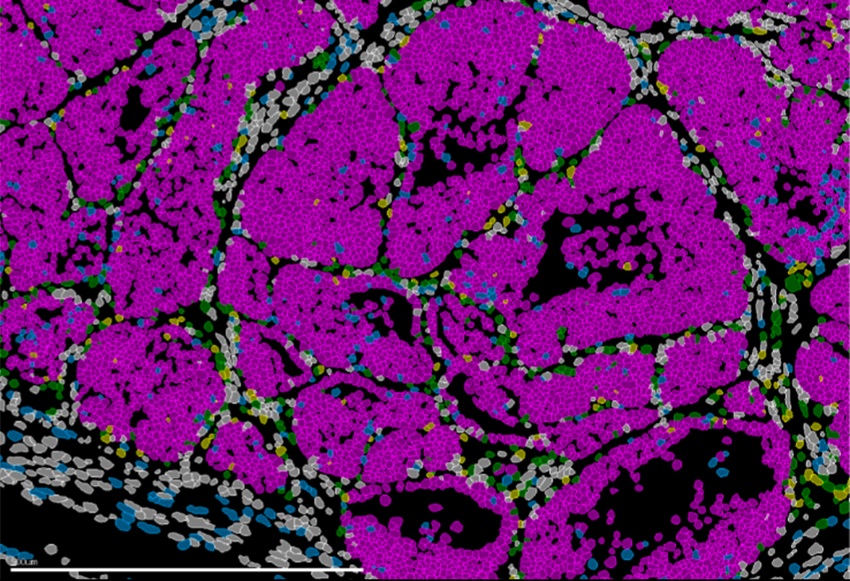

Imagen de un tumor de mama en ratón que muestra las distintas poblaciones celulares (células cancerosas en rosa). Tecnologías avanzadas de biología espacial permiten la identificación simultánea de todos los tipos celulares presentes en el tejido. Fuente: IN CSIC-UMH.

Para llegar a estas conclusiones, el equipo combinó modelos genéticos en ratón, análisis de célula única, estudios de cromatina y técnicas de transcriptómica espacial que permiten observar la organización y el comportamiento de las células directamente en el tejido tumoral. El procesamiento y análisis de los datos generados a partir de miles de células estuvo liderado por el experto en bioinformática del equipo de Nieto, el investigador Nitin Narwade. Además, en colaboración con la catedrática Gema Moreno Bueno, de la Universidad Autónoma de Madrid y la Fundación MD Anderson Cancer Center España, los investigadores analizaron muestras de pacientes con cáncer de mama y detectaron patrones similares de expresión de Prrx1, lo que sugiere que el mecanismo descrito podría tener una relevancia directa en la clasificación y el pronóstico clínico.